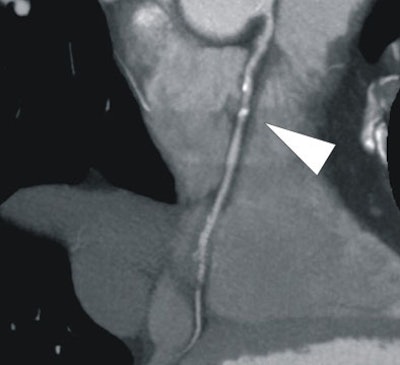

| In a 64-year-old man with chest pain, conventional catheter angiography confirmed the coronary CTA findings, and described a 50% ostial stenosis with diffuse disease throughout the vessel and a discrete 90% stenosis in the mid right circumflex artery (RCA) (arrows). |